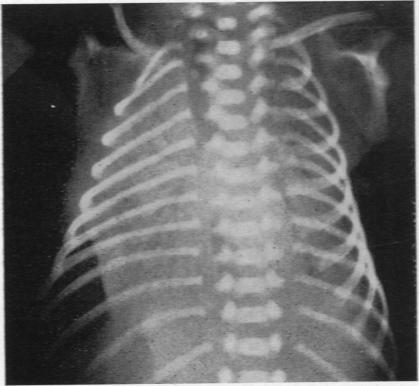

FAWCITT J

Arch Dis Child. 1956 Apr;31(156):119-23. doi: 10.1136/adc.31.156.119.